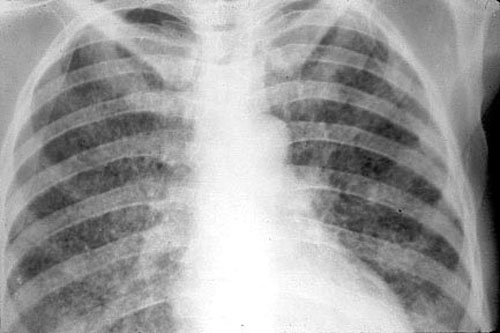

Цирротическая форма

Данный вид туберкулезного процесса отличается масштабным разрушением легочной ткани и разрастанием на ее месте соединительных волокон.

На рентгене цирротическая форма проявляется следующим образом:

• массивное затемнение высокой плотности, выглядит как ярко-белая тень;

• уменьшение объема пострадавшего легкого;

• пористый вид легочного рисунка в нижних отделах;

• смещение корня легкого и тени органов средостения в больную сторону.